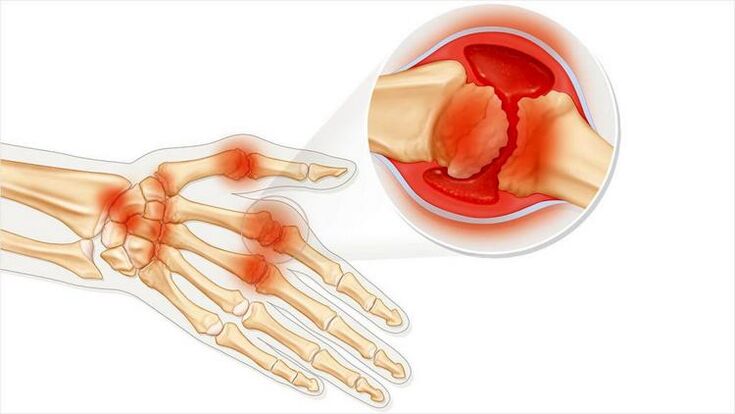

A artrite articular é unha condición de inflamación articular. Expresado principalmente como inchazo e vermelhidão. O revestimento interno da articulación é destruído, dando lugar a unha dor que adoita ser difícil de soportar.

A artrite caracterízase polas seguintes características:

- Pode producirse unha febre se a pel próxima á articulación se fai vermella.

- Cambio de aparencia da articulación.

- Tumor.

- Sensacións dolorosas ao moverse.

- Sensacións desagradables ao presionar nunha articulación.

- A artrite pode ser unha enfermidade infecciosa. A continuación, aparecen todos os síntomas correspondentes ás infeccións: un estado roto, febre, calafríos.

A artrite pode afectar unha única articulación ou varios. Ocorre con dor aguda ou gradualmente e causa unha enfermidade crónica. Entón prodúcese unha dor dolorosa.